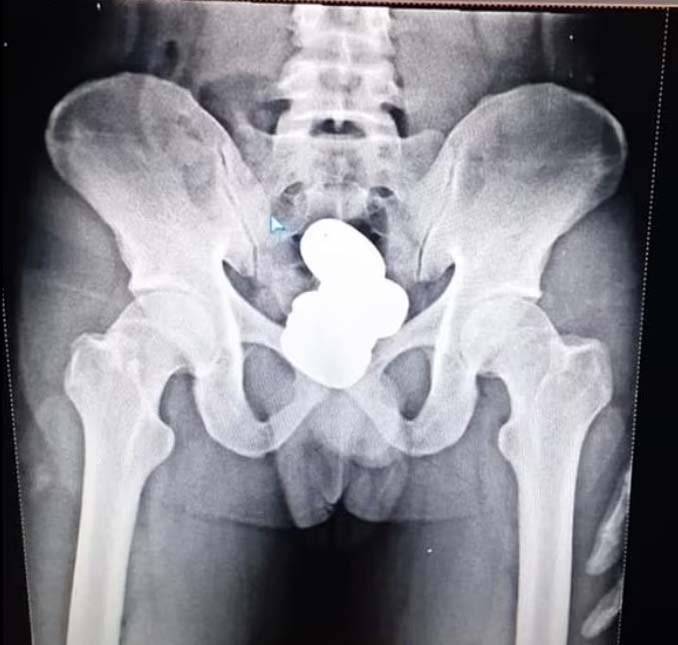

Enquanto passava no detector de metais, um oficial identificou a presença de algum material escondido em seu corpo. Após o interrogatório inicial, o homem foi levado a uma sala de exames médicos para realizar um raio-X que revelou que ele estava escondendo quatro invólucros em seu reto.

Diante da evidência, não houve mais como o homem negar seu contrabando. A matéria do britânico Daily Mail diz que Shereef confessou que trabalhava como mula e que aquele ouro não lhe pertencia. Ele também não tinha certeza do quanto estava carregando. Uma pesagem posterior constatou que havia em seu reto 909,68 gramas, o equivalente a R$ 300 mil.